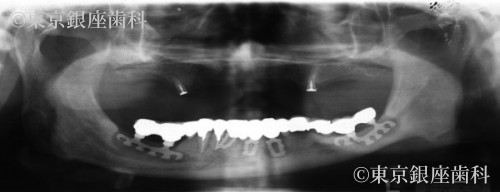

Before

30年前以上に、他院にて下顎に古いタイプのインプラント(ブレードタイプ)での全顎的な口腔機能の回復をしていた。また上顎は入れ歯を装着していた。しかし下顎のブレードタイプインプラントに感染が認められ、インプラントの動揺、周囲の骨に著しい骨吸収が認められ口腔機能の低下が認められた。また下顎管と呼ばれる、下顎の太い血管と神経が入っていいる管の近くまで骨の吸収が進んでいた。咬合に関しても歯の形がすり減り咀嚼が困難な状態となっていた。